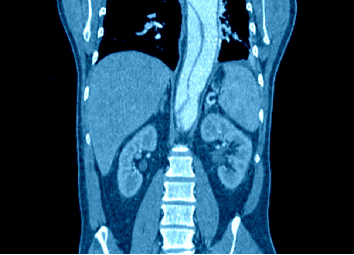

肠系膜淋巴结肿大

腹部CT可见肠系膜及腹膜后淋巴结显著增大(直径常>2cm),病理特征为泡沫状巨噬细胞浸润,PAS染色阳性,此表现对鉴别诊断具有重要价值。